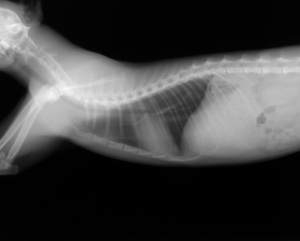

胸腔内(前縦隔)腫瘍

多剤併用療法

治療前 治療後

腫瘍(黄色の丸の部分)がなくなり、圧迫されていた気管も元の位置に戻っています。

腫瘍がレントゲンやエコー検査などで、確認できなくなっている状態(寛解)です。

寛解後も、この状態を維持する為に、必要により、治療を継続します。